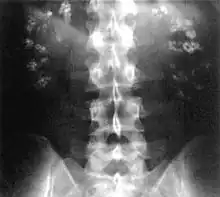

| Significant bilateral nephrocalcinosis (calcification of the kidneys) on a frontal X-ray (radiopacities (white) in the right upper and left upper quadrant of the image), as seen in distal renal tubular acidosis | |

- Nephrocalcinosis (deposition of calcium in the substance of the kidney)